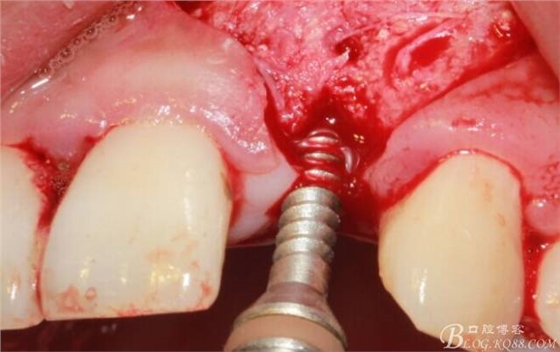

植入植體。